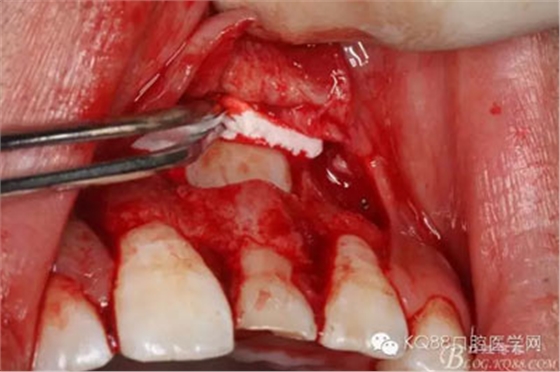

圖8.翻開牙齦粘膜瓣,可見左乳Ⅰ根方骨面隆起

圖9.超聲骨刀去除隆起的骨壁

圖10.形成梯形骨縫

圖11.掀開骨壁。摘除牙瘤及牙囊組織

圖12.摘除囊壁后,暴露出21的切端